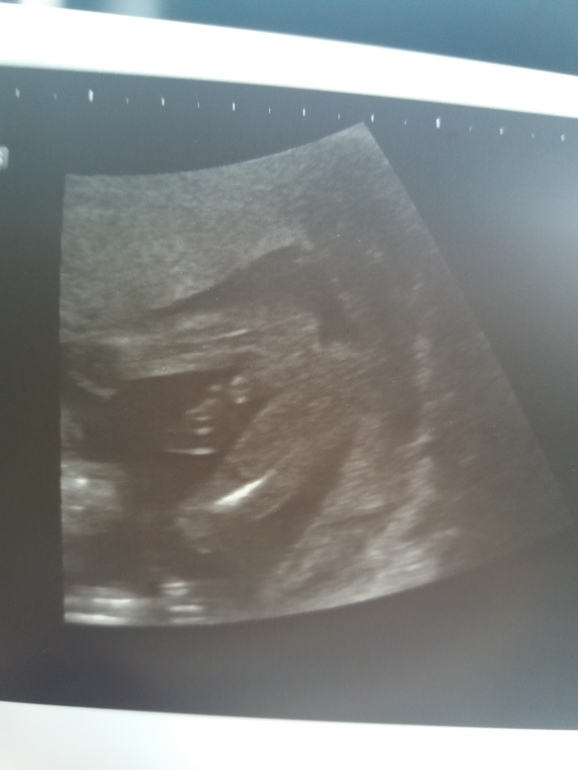

А нам вот такую девочку обещают😁😁. УЗИ где-то на 19 неделе

в 16 неделек)